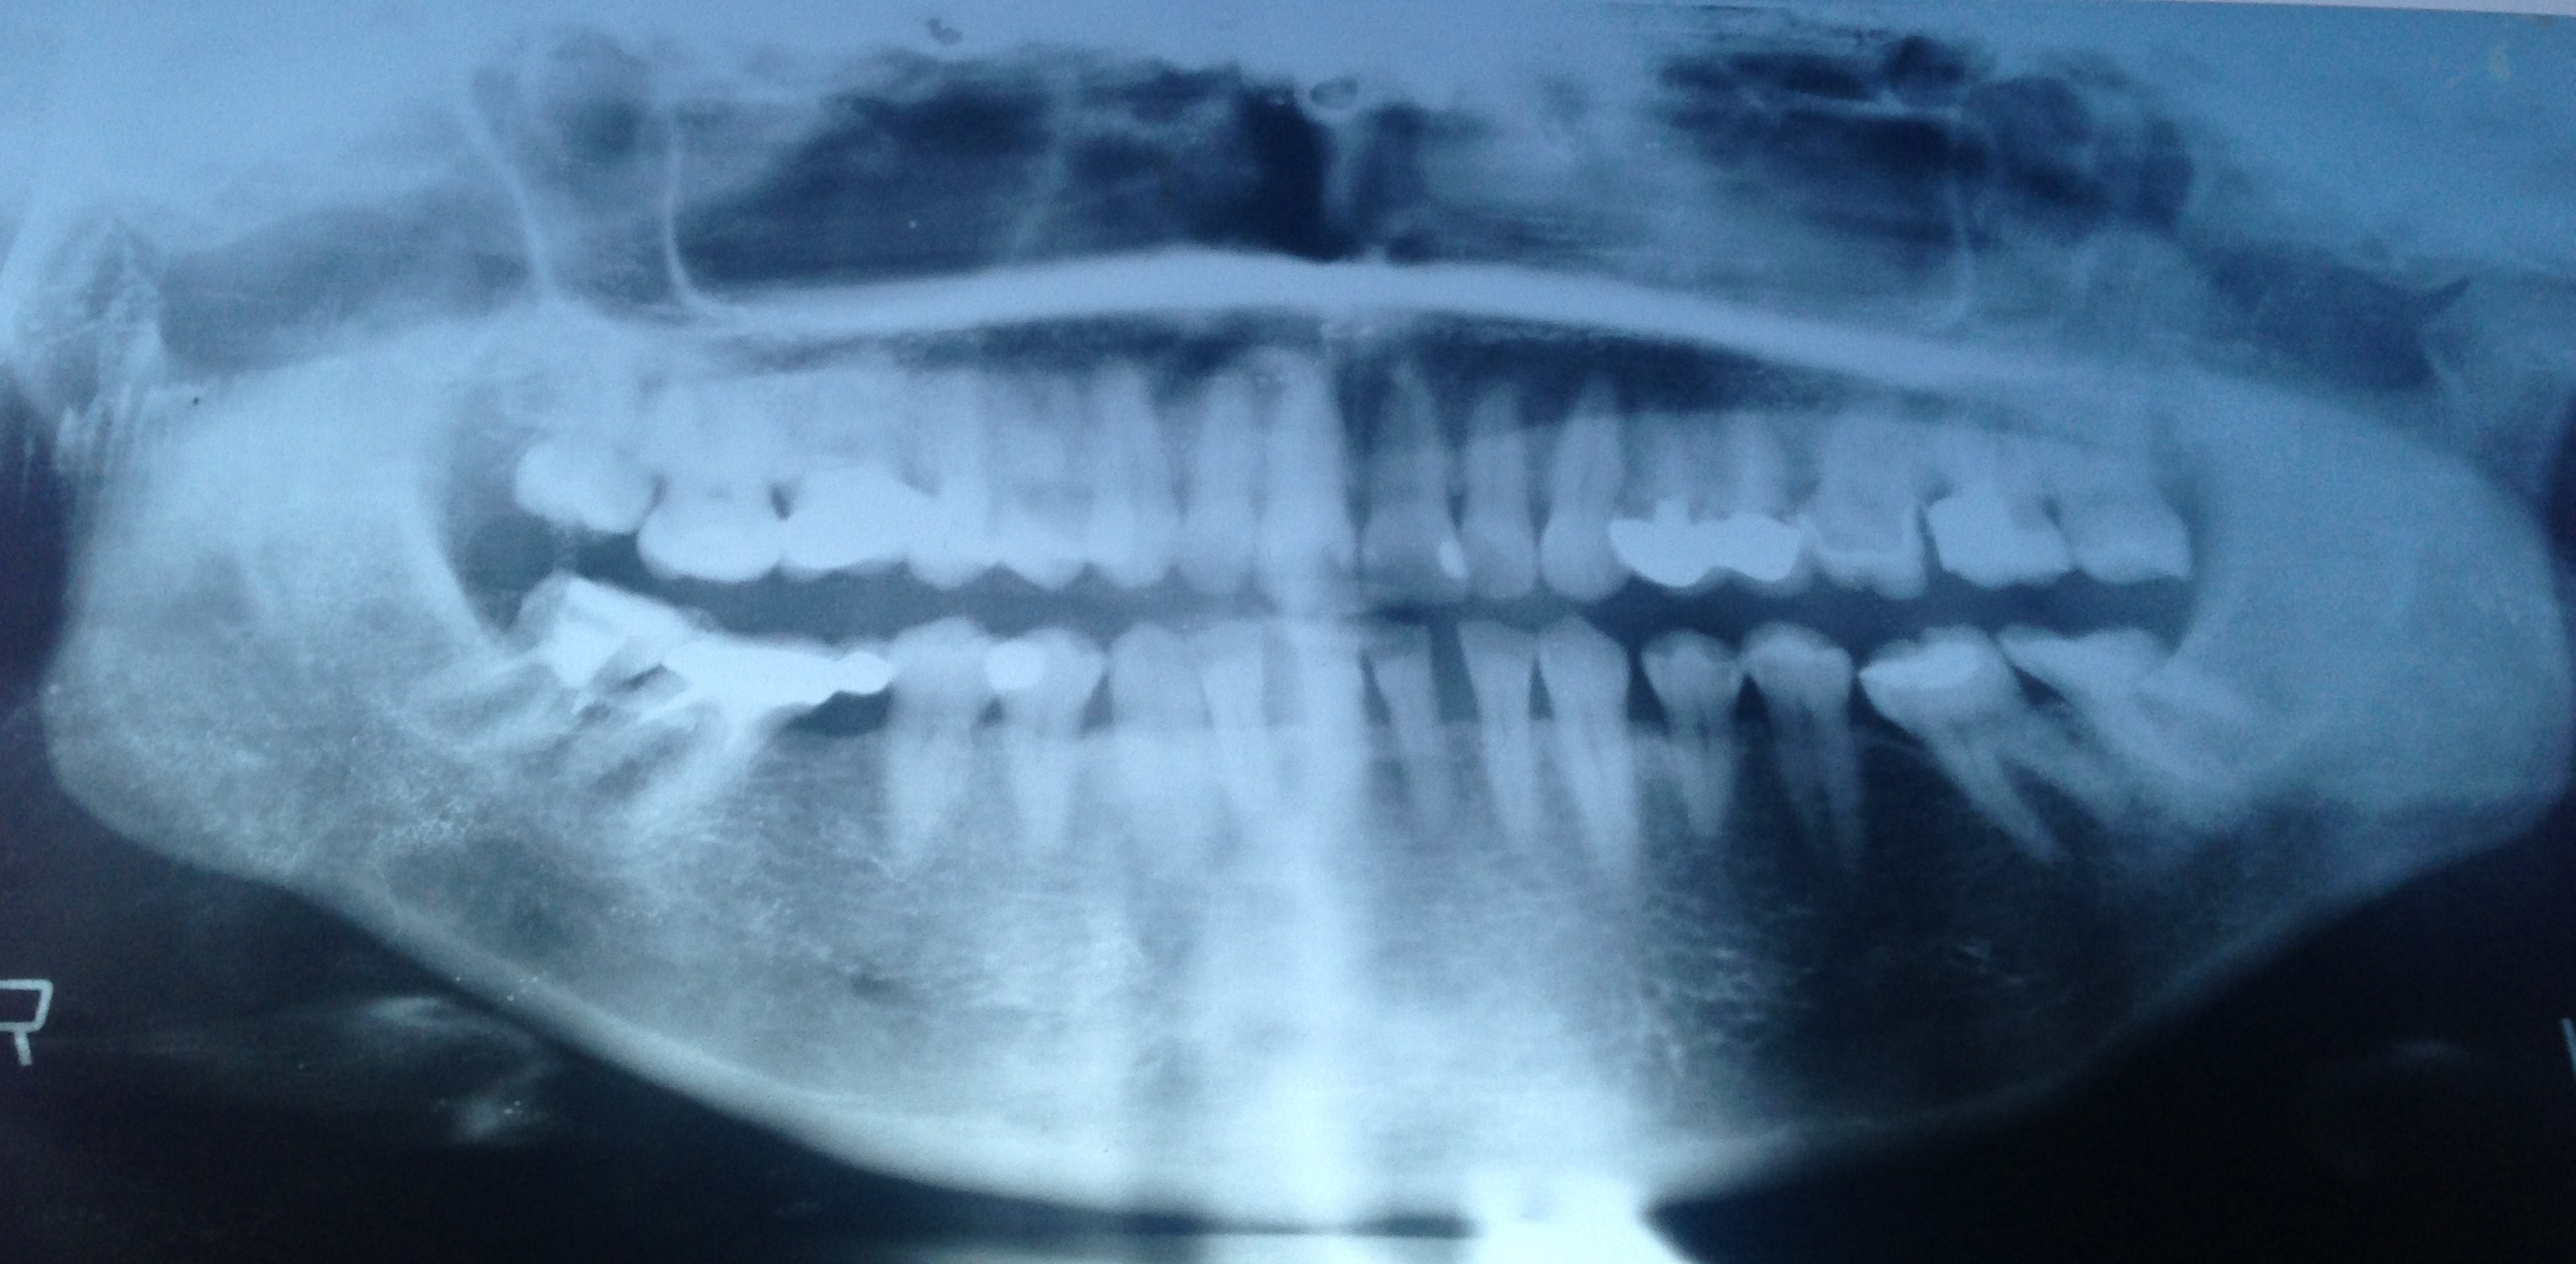

Здравствуйте. Обращение в несколько клиник принесли отрицательный результат. При осмотре в кресле и после сделанных снимков - отказ в реставрации зубов, либо оглашают цену вдвое выше, чем указана в прайс-листе, ссылаясь на трудную работу. Речь идёт о зубах улыбки. 10 верхних и 8 нижних. Всего 18 зубов.

Прикрепленые фото

Добрый день. По снимку ничего проблематичного я не вижу. Запишитесь ко мне на прием, мы с вами составим план лечения и приступим к работе. Есть определенные проблемы, но они вполне решаемы. Всего доброго.